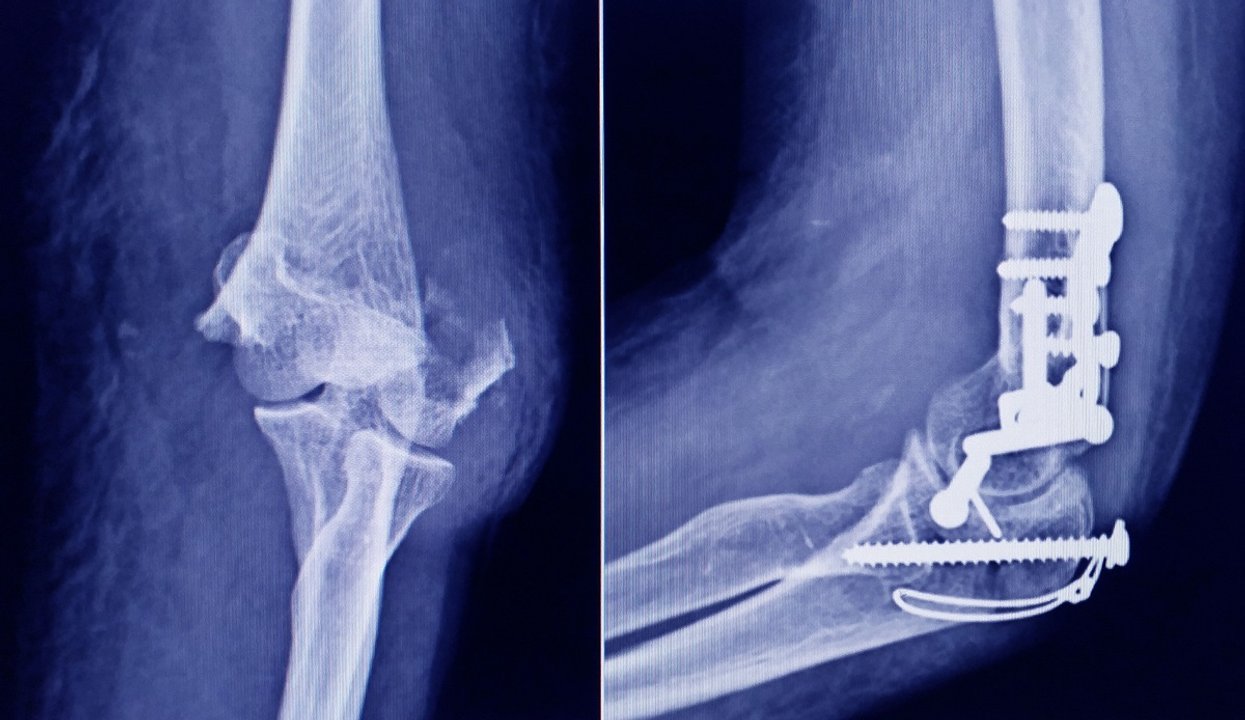

Buenos Aires, 8 enero (NA) – La Administración Nacional de Medicamentos, Alimentos y Tecnología Médica (ANMAT) advirtió a la población por un tornillo utilizado en cirugías traumatológicas debido a que es falso, por lo que su uso representa riesgo para la salud del paciente al que se lo implante.

Se trata de un tornillo utilizado en cirugías traumatológicas que fue detectado durante una inspección de control de mercado realizada en una ortopedia ubicada en la ciudad de San Miguel de Tucumán.

Dicho tornillo es producido por la firma Stryker Corporation, que se encuentra registrada ante ANMAT bajo el PM 594-139. Luego de la inspección, se exhibió la muestra recolectada ante la responsable técnica de dicha empresa, quien afirmó que se trataba de un producto falsificado.

Las autoridades de la ANMAT dieron a conocer las características del producto para su advertencia: STRYKER 10 mm X 28 mm – BIOABSORBABLE – ACL INTERFERENCE SCREW – REF 234-010-067 – LOT 90905.